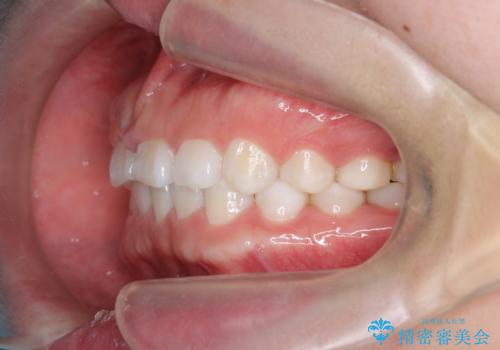

インビザライン 気になるすきっ歯の改善

- 上下顎前歯部の空隙が気になるので治したいと当院にいらっしゃった方の症例です。

非抜歯、インビザラインによる矯正治療により歯と歯の隙間および前歯の上下の隙間を閉じ切りました。